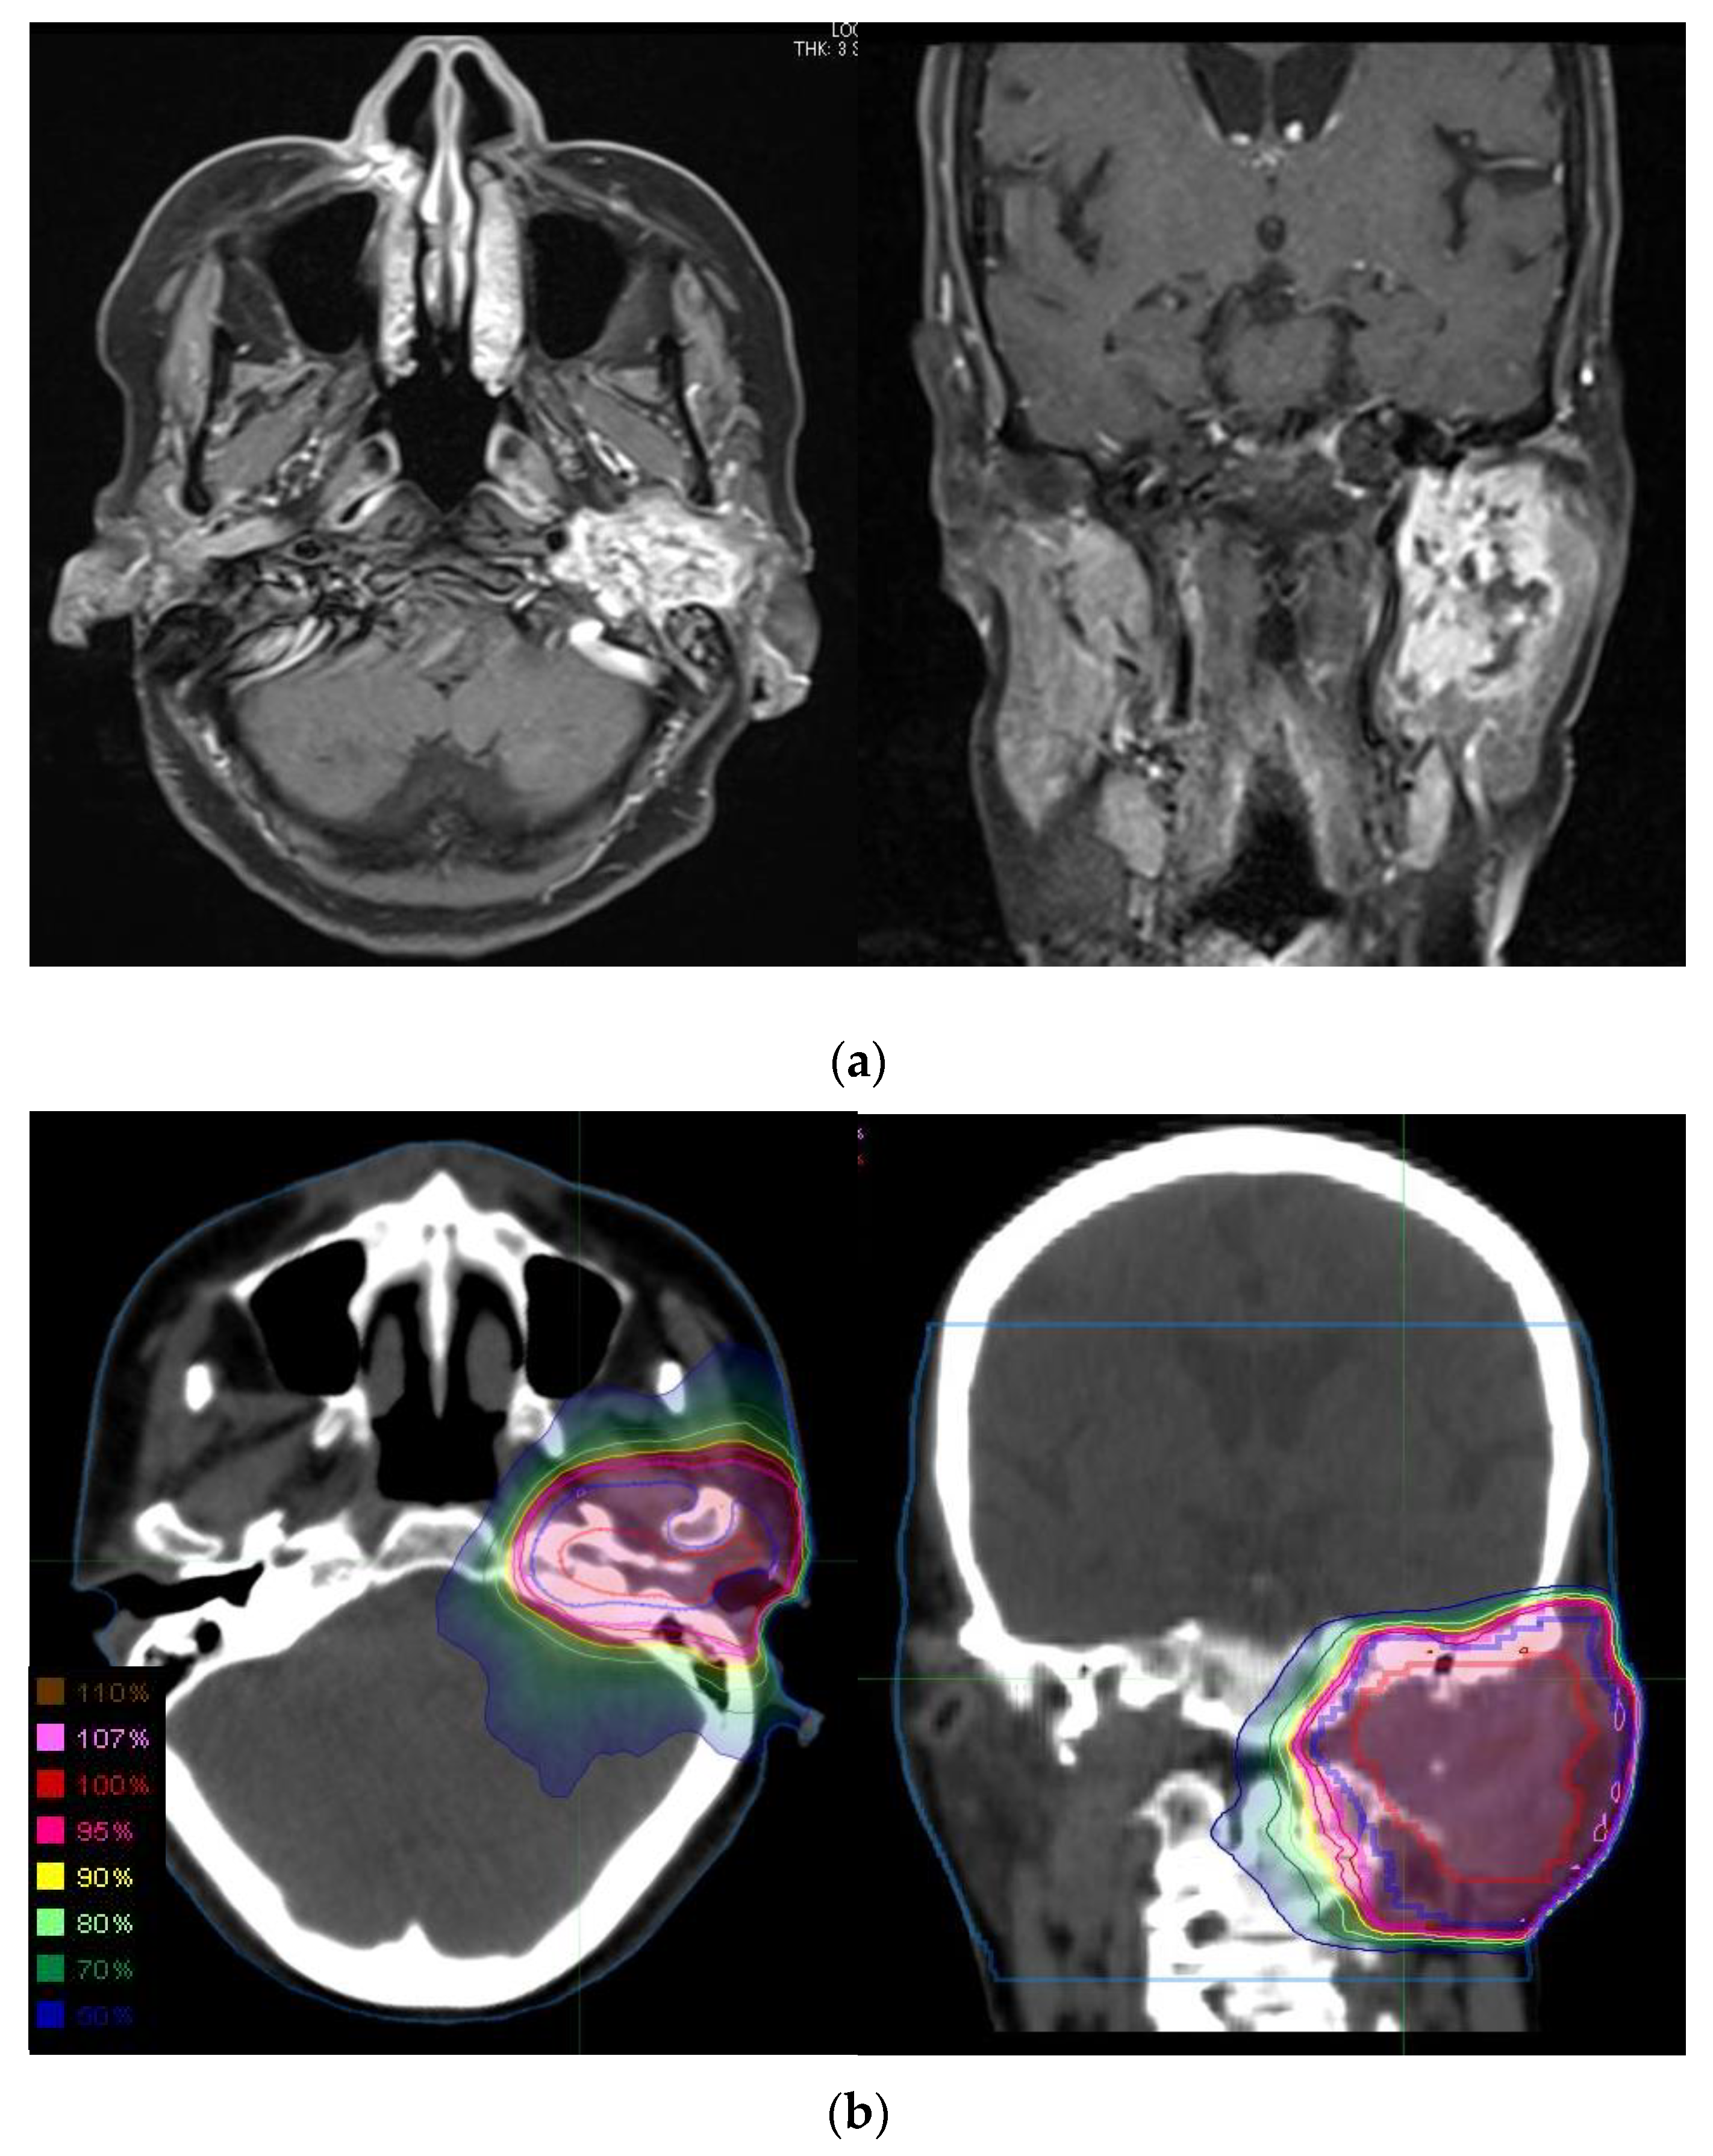

Figure 1.

Representative case of parotid gland adenoid cystic carcinoma treated with defRT using IMRT. The 75-year-old woman with left parotid gland cancer, cT4bN0M0. Left facial nerve disorder was observed. (a) MRI contrast-enhanced T1-weighted images revealed the parotid gland tumor with the extension to base of skull. The patient refused surgery and hoped to receive defRT. (b) Dose distribution of defRT using 66 Gy in 33 fractions. The GTV, CTV, and PTV are shown in red, blue, and magenta, respectively. CTV margin was extended to base of the skull considering perineural invasion. PTV margin was added to CTV to account for patient motion and the field margins. Abbreviations: defRT, definitive radiotherapy; IMRT, intensity-modulated radiotherapy; MRI, magnetic resonance imaging; GTV, gross tumor volume; CTV, clinical target volume; and PTV, planning target volume.